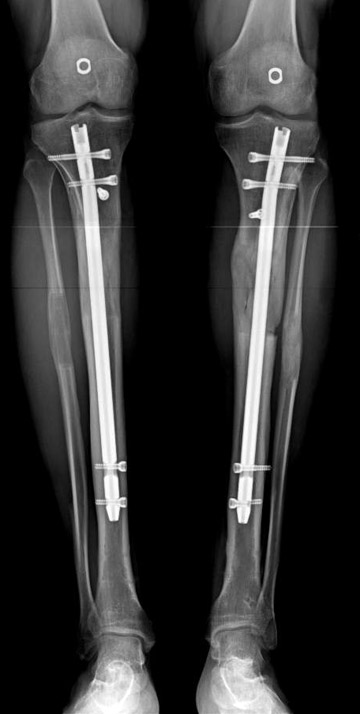

2. Step:

The application of the external fixator: Three Schanz screws are placed distally and three screws are placed proximally. At least 1 mm of distance shall remain between the screws and the nail.

Postoperative care: Distraction is commenced at day 10. 0,25 mm of lengthening is perfomed 4 times daily (every 6 hours). Hip and knee joint motion exercises begin at 1-2. day postoperatively. For many years, the treatment of lower extremity shortness has been very hard for the patient and the surgeon. The techniques developed after the introduction of Ilizarov’s distraction osteogenesis concept have pioneered a new era, and have been considered to be procedures in which previous complications are encountered much less frequently.

In selected cases, we prefer to use a combination of a unilateral dynamic axial fixator and an interlocked intramedullary nail, in order to protect the length and alignment after the completion of the lengthening procedure. As a prerequisite for this technique, the narowest diameter of the medullary cavity shall be wider than 7 mm and the length of the nail segment distal to the osteotomy site shall be at least 8 cm. after the completion of the lengthening procedure.The intramedullary nail neutralizes shear and bending forces on femur during lengthening, shortens external fixation time, and protects newly formed bone against fractures. In our series, subtrochanteric osteotomy was performed in one case. No varus angulation occured despite the intramedullary nail.